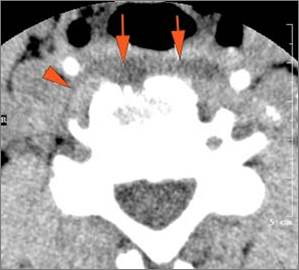

Vascular Findings

There is evidence of thrombus, thrombophlebitis or other occlusive or inflammatory process of the jugular vein or smaller venous tributaries. [Yes/No]

There is evidence of thrombus, thrombophlebitis or other occlusive or inflammatory process smaller jugular venous tributaries. [Yes/No]